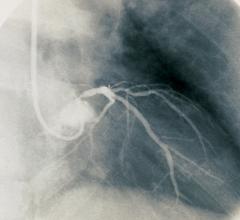

Vital Images Inc. will debut its U.S. Food and Drug Administration (FDA) 510(k)-cleared CT Myocardial Perfusion application at the 10th annual scientific meeting of the Society of Cardiovascular Computed Tomography (SCCT). The meeting will be held in Las Vegas July 16-19.